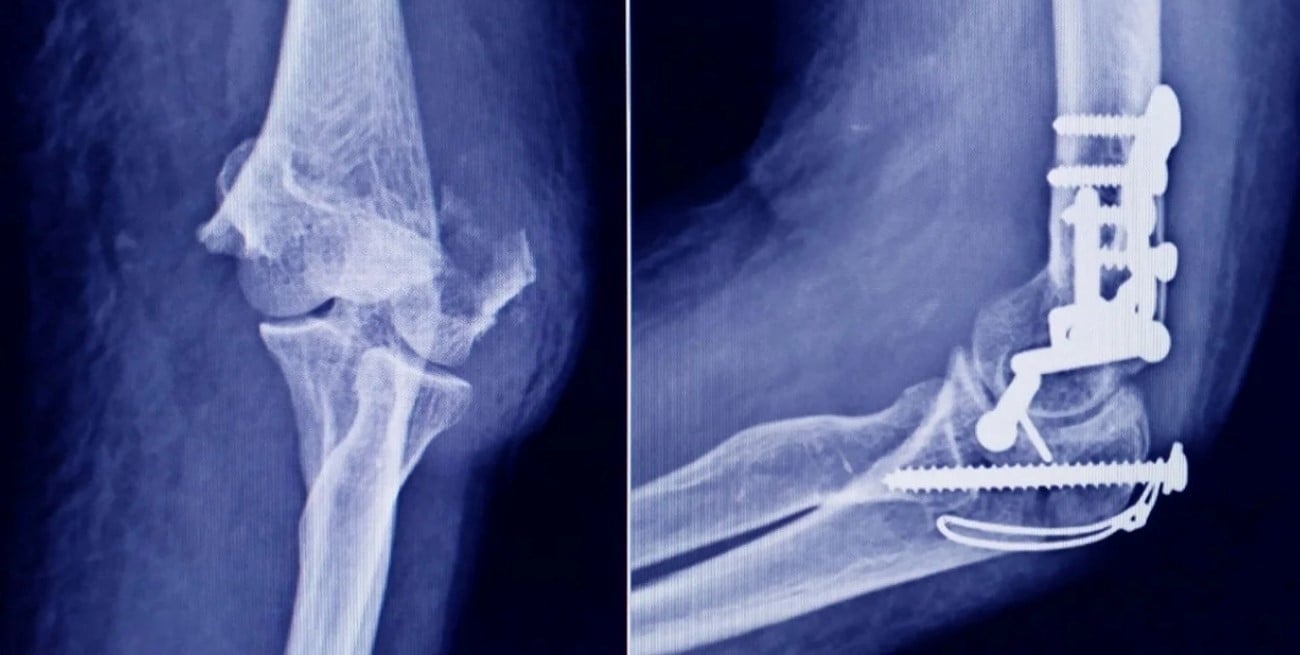

La Administración Nacional de Medicamentos, Alimentos y Tecnología Médica dispuso la prohibición del uso, comercialización y distribución de una serie de insumos médicos utilizados en traumatología, luego de detectar graves irregularidades durante una inspección en un establecimiento de la provincia de Tucumán.